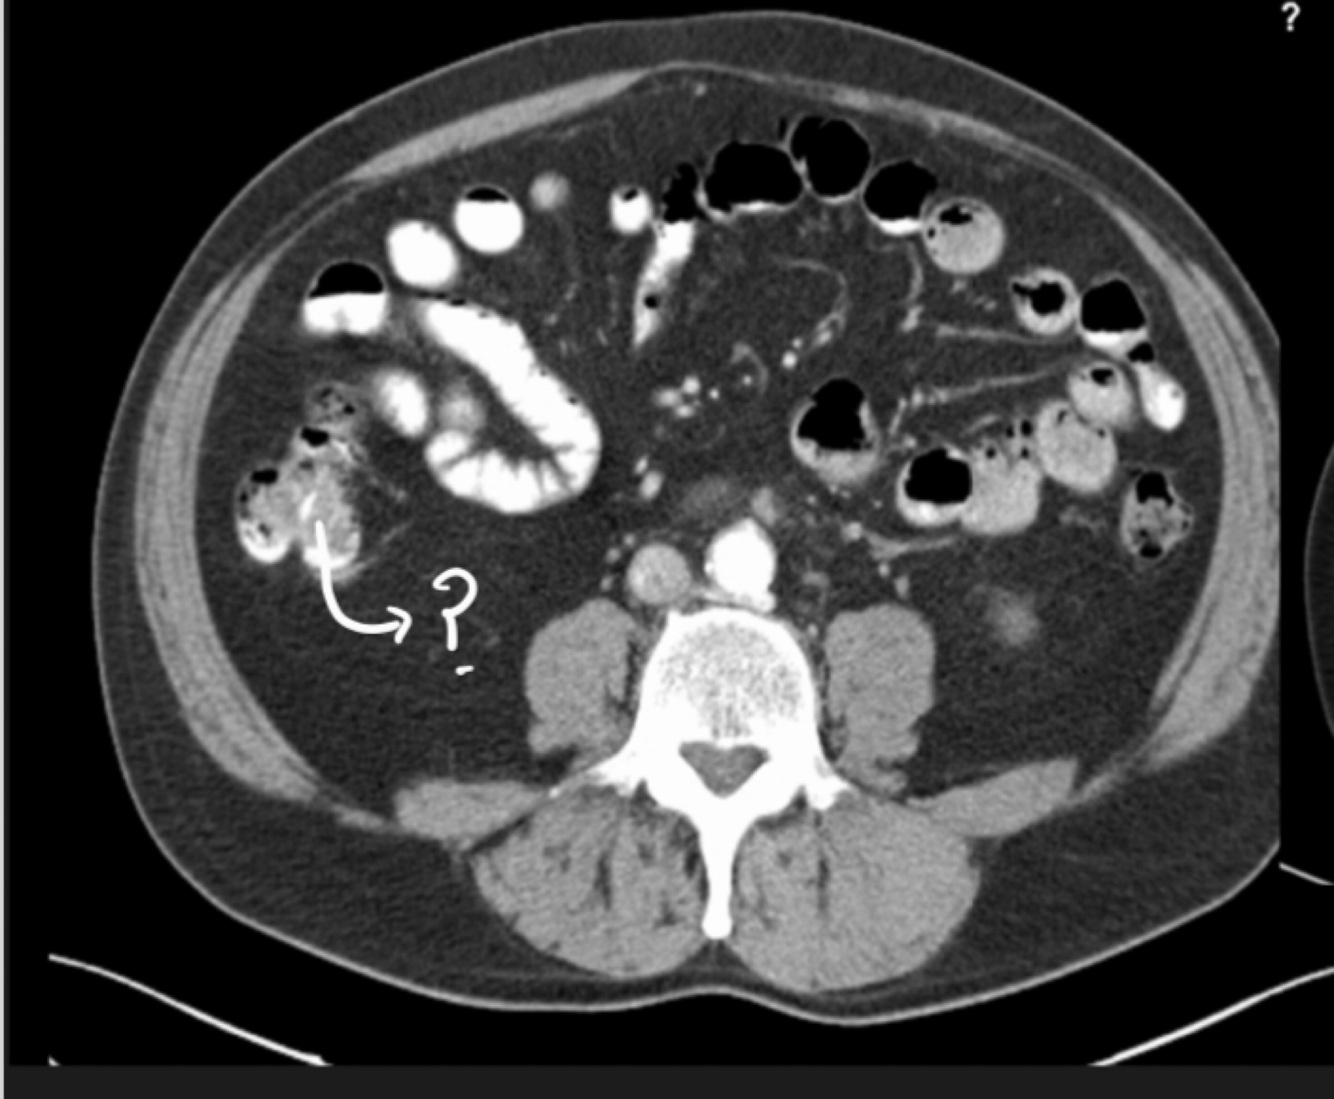

Q

Name the marked structure

A

Ascending colon

The 3rd part of the duodenum is anterior to … and behind the

Aorta and superior mesenteric artery

26

Name the structure

Superior mesenteric artery